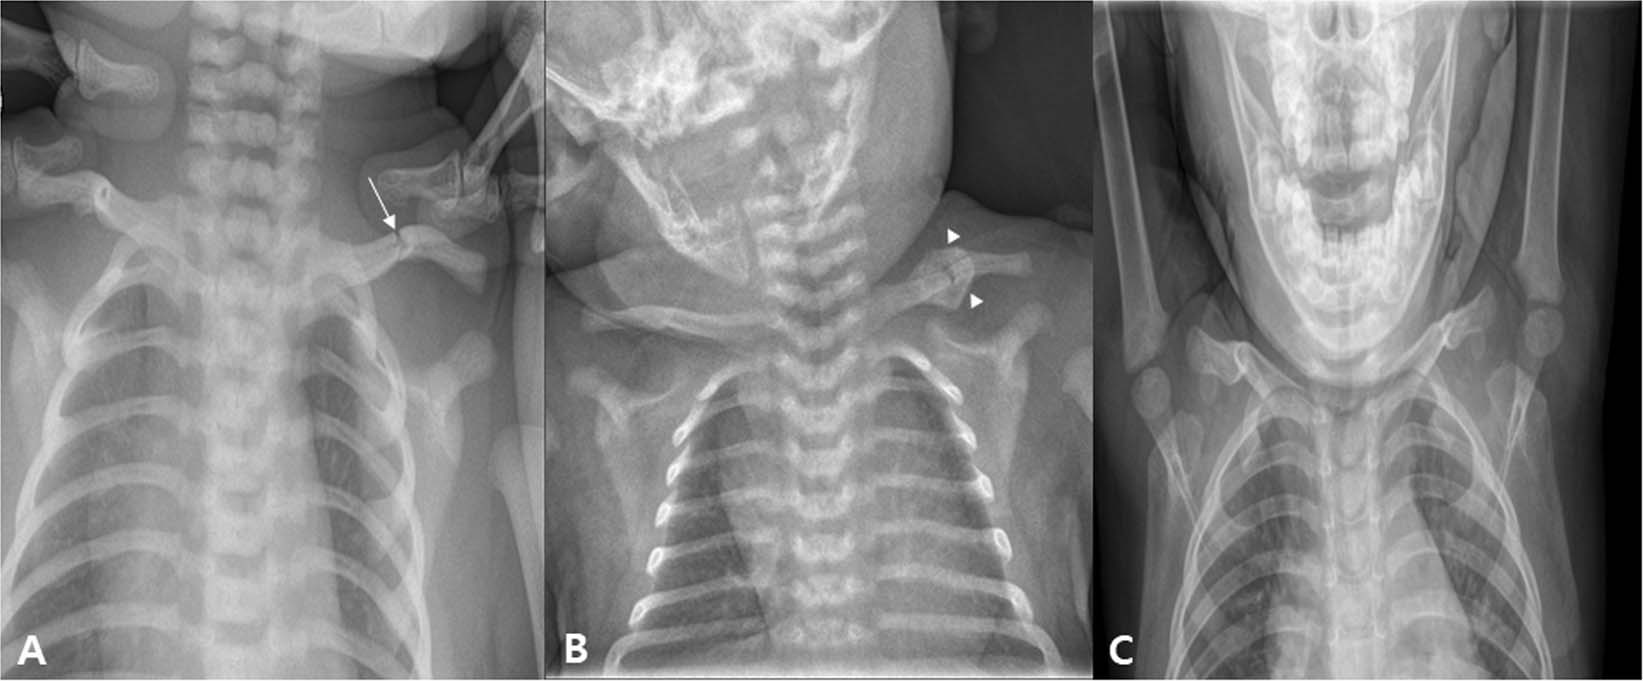

Figure 3

An infant who visited our hospital for left torticollis. In ultrasound examination, there was muscular fibromatosis in right SCM. (A) At 4 days after birth, left clavicular fracture was seen (arrow). (B) Follow-up plain radiograph at 21 days after birth. A callus formation was seen around fracture site of left clavicle (arrowhead). For clavicular fracture, only a conservative treatment was performed except stretching exercise and home education for right CMT. (C) Follow-up plain radiograph at 22 month after birth. Callus formation was disappeared, and it is difficult to find the difference between left and right clavicle. CMT; congenital muscular torticollis, SCM; sternocleidomastoid.